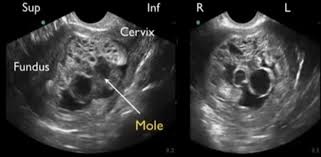

Ilustrasi medis pada kasus hamil anggur (mola hidatidosa). (Foto: Dok. Tzu Chi Hospital)

Secara medis, hamil anggur adalah komplikasi kehamilan yang langka di mana sel telur yang telah dibuahi berkembang secara tidak normal. Bukannya tumbuh menjadi janin dan plasenta yang sehat, sel-sel tersebut justru membentuk sekumpulan kista (kantong berisi cairan) yang menyerupai gerombolan buah anggur di dalam rahim.